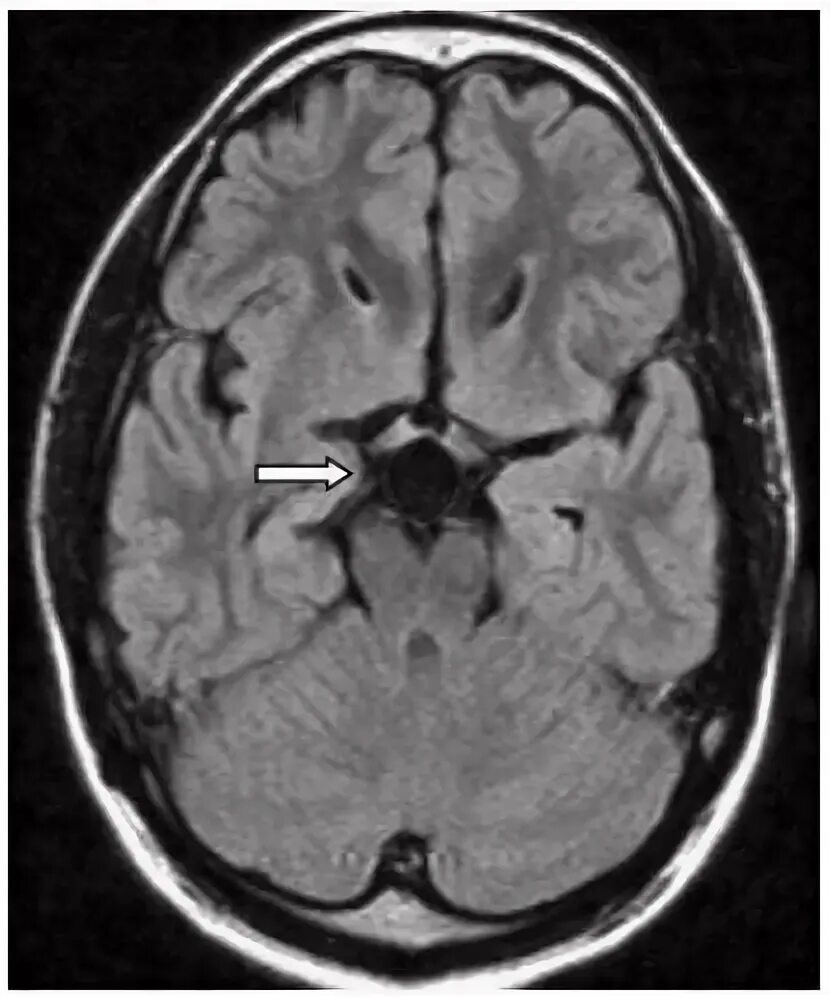

Что значит пространства вирхова робина